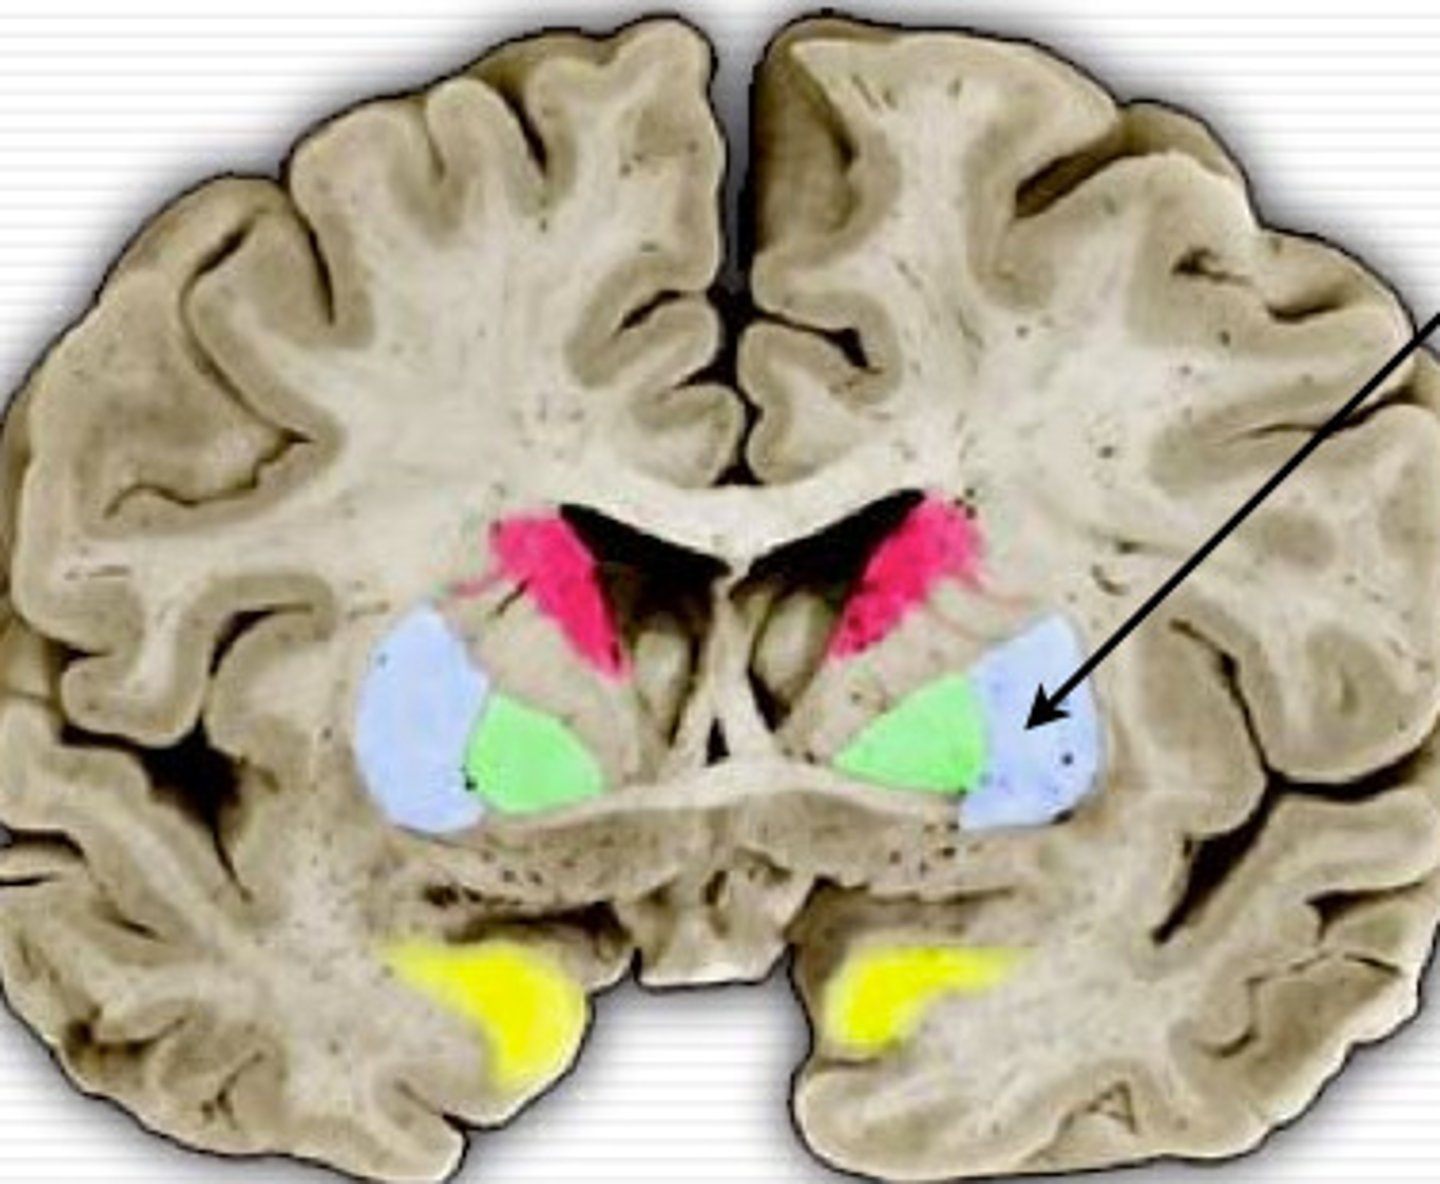

thalamus

heart shaped, deep in the brain, hugs the third ventricle. Referred to as the relay center.

hypothalamus

anterior+inferior to the thalamus, U-shape below the third ventricle, medial to globus pallidus. maintains homeostasis.

Basal Ganglia

structures in the forebrain that help to control movement. Composed of three main parts: the caudate nucleus, the putamen, and the globus pallidus

Caudate nucleus

One of the major nuclei that make up the basal ganglia. Head: Anterior to the thalamus, forming the lateral wall of the lateral ventricle.

Body: Extends posteriorly and laterally from the head, parallel to the thalamus.

Tail: Curves inferiorly and medially, lying above the temporal horn of the lateral ventricle.

Putamen

involved in motor control and learning

Globus Pallidus

more medial than putamen, appears with the third ventricle.

internal capsule

White matter pathway is lateral to the caudate nucleus, between the caudate and the putamen (and globus pallidus). It carries primarily motor fibers, including corticospinal tract fibers.

lateral ventricle

A complexly shaped lateral portion of the ventricular system within each hemisphere of the brain.

anterior horn of lateral ventricle

located in the frontal lobe and is the part of the lateral ventricle that lies in front of the interventricular foramen

body of lateral ventricles

located in the parietal lobe, situated between the anterior and posterior horns.

inferior horn of lateral ventricle

located in the temporal lobe of the brain. It is the largest of the three horns and extends from the atrium, curving anteriorly and inferiorly to go under the thalamus and into the temporal lobe

posterior horn of lateral ventricle

located in the occipital lobe of the brain, projecting backward. It is the most posterior part of the C-shaped lateral ventricle and lies deep within the occipital lobe.